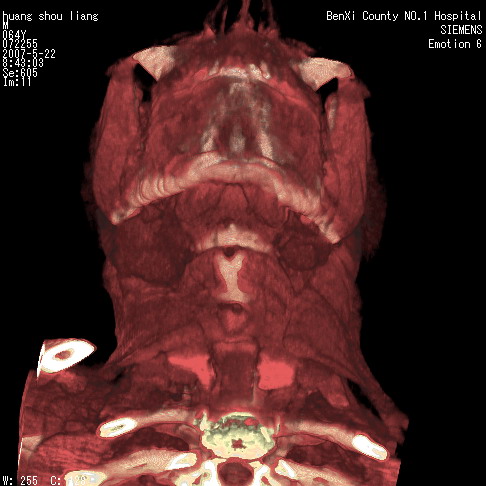

男性,64岁。颈部包块8年。最近增大。

对不起大家,可能是片子发太多有点乱,正常腮腺在下颌角的外侧,颌下腺在下颌体的中部内侧,本例在下颌角内侧偏下,和腺体一点关系都没有,从vrt和mpr上可以很明显看出来,再者肿块是好多粘连在一块的,大家在仔细看看,左侧可能也是吧,我还是考虑为肿大的淋巴结融合在一块,但性质??????

多考虑颌下腺混合瘤恶变,建议进一步检查,另外楼主重建图像很漂亮。

大家好,病理结果出来了,如大家所说,颌下腺混合瘤。